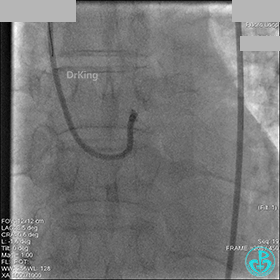

冠脉造影

入院次日冠脉造影显示粗大左主干末端中度狭窄,前降支开口严重狭窄,回旋支与前降支角度大,弥漫性长病变,严重狭窄,粗大右冠脉近中段弥漫性中重度狭窄。由于病变复杂,造影结束后先下台,择期再行介入治疗。